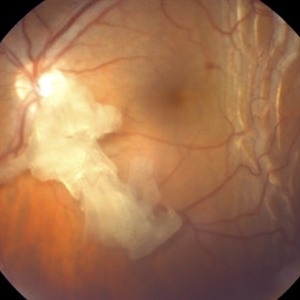

Anterior Ischemic Optic Neuropathy and Choroidal Ischemia

Mar 1 2014 by Homayoun Tabandeh, MD, FASRS

Fundus fluorescein angiogram of a patient with arteritic anterior ischemic optic neuropathy and choroidal ischemia associated with giant cell arteritis.

Condition/keywords: anterior ischemic optic neuropathy